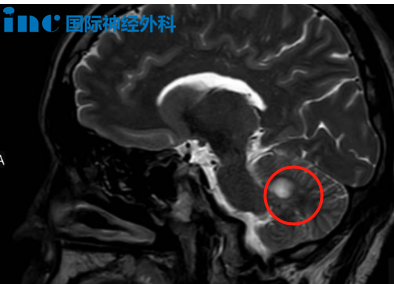

对于青少年患者,治疗从来不只是挽救生命——更是在守护他们尚未展开的人生。每一次治疗决策都关乎他们的生长发育、未来生存质量,甚至几十年的幸福。2020年,19岁的飞宇因突发剧烈头痛、喷射状呕吐,被确诊为松果体区肿瘤并继发脑积水,紧急接受脑室腹腔分流术后症状缓解。然而,肿瘤悄然增大,危机再度降临:视力显著下降,视野缺损,MRI揭示一个40×25×31mm的巨大肿瘤已完全占据第三脑室,从室间孔向下压迫中脑——他的未来,正在被一点点吞噬。

“需要手术,且越快越好!”巴教授认为。四十年的经验和技术,他曾成功为类似患者实现肿瘤全切且手术风险可控。“当然不能保守治疗!对19岁的患者进行盲目放化疗也是禁忌!这既无法解决肿瘤,还可能给他带来新的严重问题。”——人生只有一次,治疗的终极目标不仅是切除肿瘤,更是让他未来的人生,依然拥有无限可能。